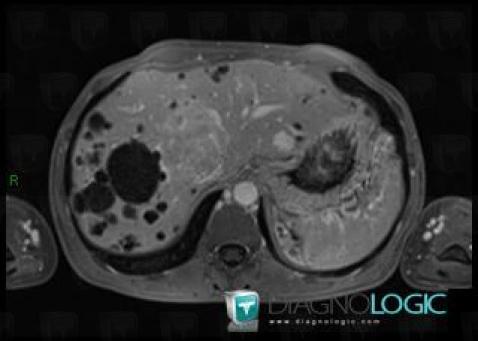

Polykystose rénale, Rein, IRM

Voici les informations spécifiques à l'image clé ci dessus:

- Diagnostic Polykystose rénale, Localisation(s) Rein, comportant les gammes Masse rénale en hypersignal T2, Masse rénale kystique, Maladie kystique rénale

- Diagnostic Polykystose rénale (lié à Kyste ), Localisation(s) Rein, comportant les gammes Masse rénale exophytique